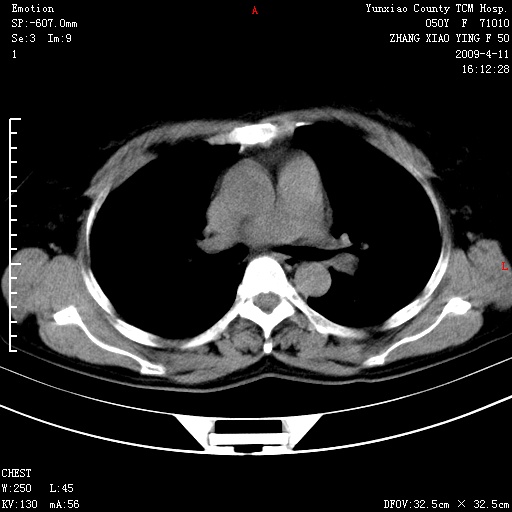

标题: CT19324:胸闷1周伴咳嗽 [打印本页]

标题: CT19324:胸闷1周伴咳嗽

病灶周围肺纹受压移位走行较柔和,余肺里实质均匀,纹理如常,肺间质无显著纤维化,支持考虑孤立性肺囊肿

考虑右肺中叶肺囊肿。